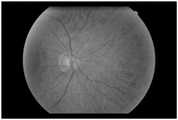

FIG. 2 is a schematic view of an original fundus image in the detection method of the present invention.

s1, acquiring an original retina color fundus image (shown in figure 2) and marking;